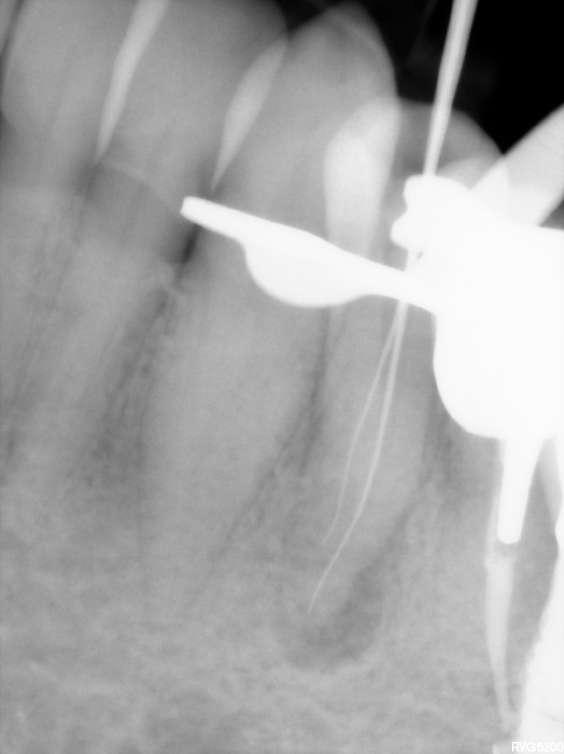

Divergierende Kanäle (zwei Kanäle, die zusammen beginnen und sich dann im mittleren / apikalen Teil der Wurzel trennen) stellen ein klinisches Problem in der Endodontie dar, insbesondere bei der Verwendung traditioneller NiTiInstrumente. Aufgrund des superelastischen Verhaltens der Legierung können die Instrumente dem gleichen Kanal folgen (und zwar dem, der gerader ist) aber es ist schwieriger, den zweiten zu finden, insbesondere dann, wenn man den Eingang unmöglich wegen seiner Tiefe in der Wurzel sehen kann.

Der vorliegende Fall zeigt den klinischen Vorteil der Verwendung einer Einzelfeil-Reziprokationstechnik mit einer wärmebehandelten vorgebogenen martensitischen Feile (Edge One Fire) bei der Behandlung divergierender Kanäle auf.

Untere Prämolaren können manchmal zwei oder drei Kanäle aufweisen. Eine solche ungewöhnliche Anatomie ist oft mit engen, stark gekrümmten, konfluenten oder divergierenden Kanälen verbunden. Der letzte Fall ist sehr komplex und erfordert in der Regel den Einsatz von Instrumenten, welche in zwei verschiedenen Kanälen ( daher flexibel und präbendal ) mit unterschiedlichen Winkelstellungen ausgerichtet werden können. Ein angemessener Gleitpfad hilft auch bei der NiTi-Formung, er löst aber nicht immer das Problem. Daher wurde im vorliegenden Fall die primäre EinzelfeileReziproziertechnik EOF verwendet. Die Instrumente wurden in ihrem apikalen Teil vorgeformt, in die beiden verschiedenen Kanäle eingeführt und dann aktiviert. Die Wahl der Instrumente war effektiv, weil die mechanischen Eigenschaften des EOF-Primärs (flexibel und vorgebogen) es ermöglichen, präzise und einfach in jeden Kanal eingeführt zu werden und diese dann zu behandeln. Die Verwendung einer einzigen Feiltechnik ermöglichte es, sich der Herausforderung eines divergierenden Kanals nur einmal zu stellen, was Zeit spart und die Komplexität reduziert. Die Verwendung traditioneller Instrumente kann in vielen Fällen helfen, den Weg mit kleineren und flexibleren Instrumenten zu finden, aber nicht mit größeren. Durch die Verwendung von nur einer Feile erwies sich das gesamte Verfahren als einfacher und schneller, sodass beide Kanäle korrekt geformt, gereinigt und abgedichtet werden konnten.

Eine Single-File-Reziprozierungstechnik mit einer wärmebehandelten vorgebogenen martensitischen Feile (Edge One Fire) erwies sich als ausgezeichnete, einfache und schnelle Option für die Instrumentierung von divergierenden Kanälen.

Komplexe Kanalanatomien erfordern den rationalen Einsatz von NITIInstrumenten, indem die beste Option für den Fall in Bezug auf Effizienz, Sicherheit und Einfachheit ausgewählt wird. Die mechanischen Eigenschaften von EOF ermöglichen es, divergierende Kanäle mit großer Wirksamkeit zu behandeln, wobei iatrogene Fehler oder Komplikationen vermieden werden können.